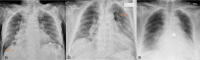

A wide spectrum of conditions, from life-threatening to non-urgent, can manifest with acute dyspnea, thus presenting major challenges for the treating physician when establishing the diagnosis and severity of the underlying disease. Imaging plays a decisive role in the assessment of acute dyspnea of cardiac and/or pulmonary origin. This article presents an overview of the current imaging modalities used to narrow the differential diagnosis in the assessment of acute dyspnea of cardiac or pulmonary origin. The current indications, findings, accuracy, and limits of each imaging modality are reported. Chest radiography is usually the primary imaging modality applied. There is a low radiation dose associated with this method, and it can assess the presence of fluid in the lung or pleura, consolidations, hyperinflation, pneumothorax, as well as heart enlargement. However, its low sensitivity limits the ability of the chest radiograph to accurately identify the causes of acute dyspnea. CT provides more detailed imaging of the cardiorespiratory system, and therefore, better sensitivity and specificity results, but it is accompanied by higher radiation exposure. Ultrasonography has the advantage of using no radiation, and is fast and feasible as a bedside test and appropriate for the assessment of unstable patients. However, patient-specific factors, such as body habitus, may limit its image quality and interpretability. Advances in knowledge This review provides guidance to the appropriate choice of imaging modalities in the diagnosis of patients with dyspnea of cardiac or pulmonary origin.